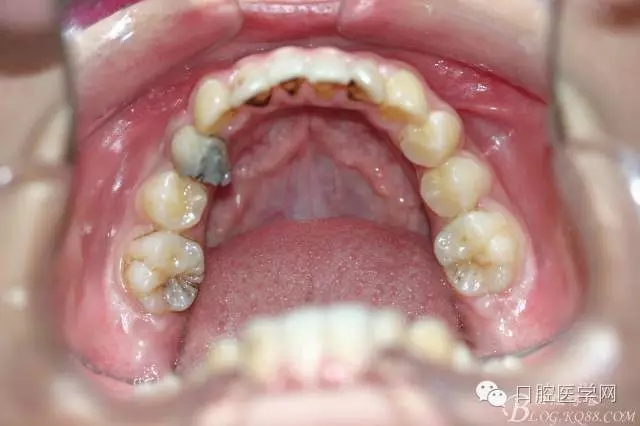

正畸查:替牙合。第一恒磨牙中性合。上牙弓尖圓型下牙弓方圓型。前牙覆合3度覆蓋7.5mm。下前牙咬到上舌側(cè)牙齦。上頜擁擠4.0mm,下頜擁擠

3.0mm。上頜稍前突下頜后縮,上下唇前突,上前牙覆蓋下唇,下唇外翻。面下三分之一過短,頦唇溝明顯,開唇露齒,頦饜窩明顯。顳下頜關(guān)節(jié)開閉口無彈響,無壓痛,開口型開口度正常。